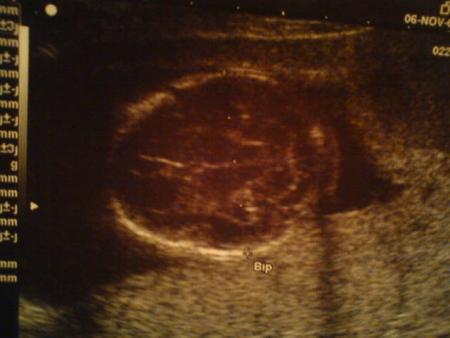

Son cerveau vu du dessus !!! C'est magique ce qu'on voit aux échos !!!

Son gros gros bidon !!!

Et oui ce gros truc tout rond c'est son ventre !!! A croire qu'il veut rivaliser avec moi, et la tache noire c'est son estomac !!! Ca prouve qu'il est comme papa et maman, un pti gourmand qui adore téter le liquide amniotique, c'est pour ça qu'on voit si bien son estomac!!!

6 novembre 2008 : visite du 4ème mois chez le gynéco

Voilà des nouvelles de bébé et de maman ...

Alors côté maman, rien de neuf, j'ai mal aux hanches car je porte bébé très bas et que mon ventre pousse vite, mais aucun solution pour moi ....juste me dire que bébé pousse bien et que je dois patienter et faire attention, ne pas forcer ou porter (même ma puce d'amour...) c'est tout ...et pour les contractions : m'allonger dès que j'en ai ...donc toujours pas porter et y aller doucement ...

Côté bébé il est en pleine forme !!! Il a hérité par le gynéco du surnom de "bon steack"!!! car il fait déjà 234gr !!! brave bête hihihi il a de belles jambes fines et un gros bidon !!! hihi. Il gigote bien et son coeur bat bien et très très vite...

Quant à son poids, bébé grossit bien mais maman non ;) c'est super cool je suis toujours a  -1.5kg par rapport à mon poids d'avant grossesse, c'est top !!!

et sur la photo je vous présente le profil de "presque 4" comme dit son papa et on voit bien son pti coeur aussi !!!

(la tâche noir )